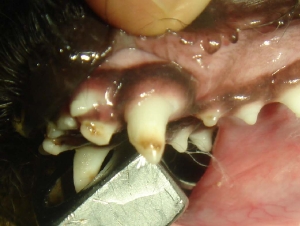

歯石除去 例1

犬歯のエナメル質に形成不全が認められます。不全症をおこした部位は茶色く変質し、超音波にて洗浄してもこれ以上は綺麗になりません。

変質した茶色い部分を掘削します。掘削した部位は段差が生じます。

掘削し、段差が生じている部分を青くトレースしております。

段差部位をレジンにて修復しております。その後、コーティングを行うことで、段差部位における経年の汚れも減少します。